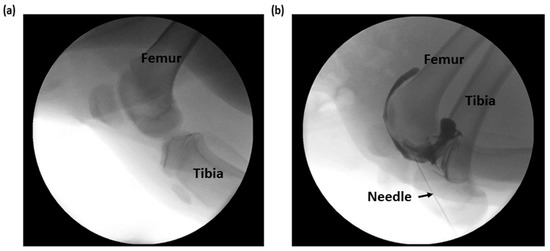

2.2. Experimental Setup

3.3. Impedance Monitoring of the Needle Tip in the Intra-Articular Cavity